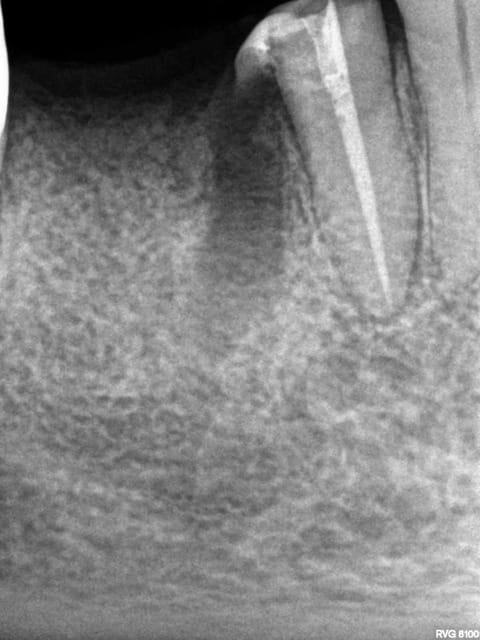

Exemple endo 45 taille empreinte. ( mac spaden) 35 mn.

Radio cone en place, cone scellé, mac spaden, logement tenon.